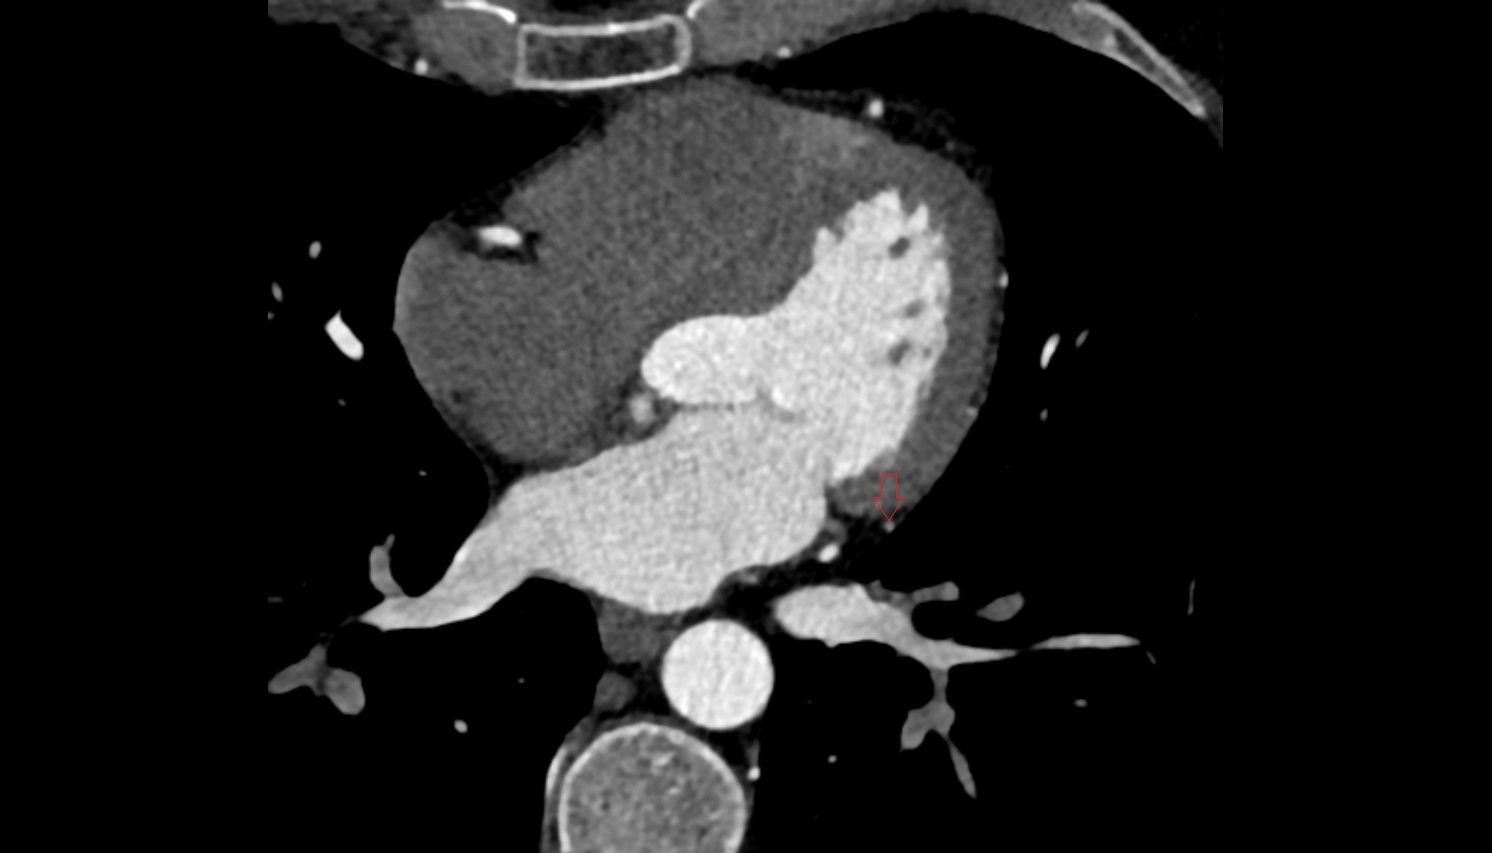

- Left anterior descending artery (LAD)

- Circumflex artery (LCx)

- Left main coronary artery (LMCA)

- Right coronary artery (RCA)

- Right posterior descending coronary artery (Right PDA)

- Distal left anterior descending artery (dLAD)